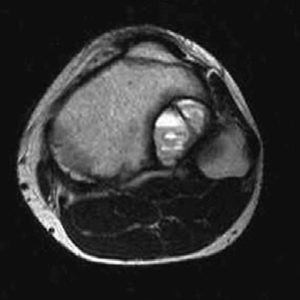

Orthopaedic oncology Structured oral examination question 6: Osteosarcoma EXAMINER : This young lad presented…

Orthopaedic oncology Structured oral examination question 5: Chondrosarcoma EXAMINER : This is a very fit and…

oncology Structured oral examination question 7: Aneurysmal bone cyst EXAMINER : This is a 20-year-old man wh…